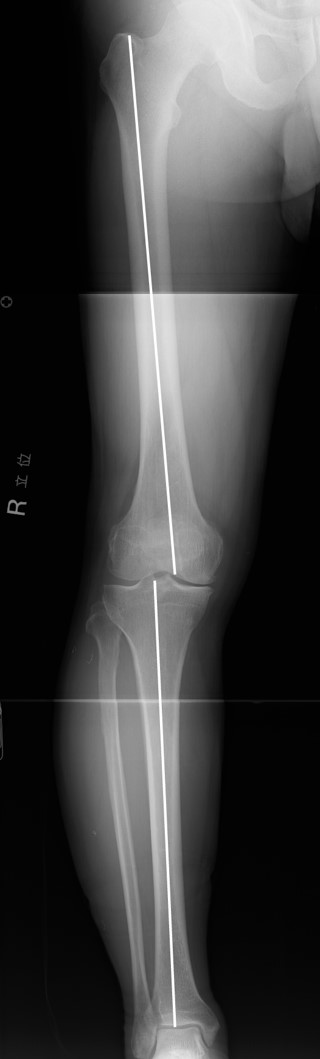

• ナビゲーション高位脛骨骨切り術

3. ナビーゲーション高位脛骨骨切り術

4. ナビゲーション3-1